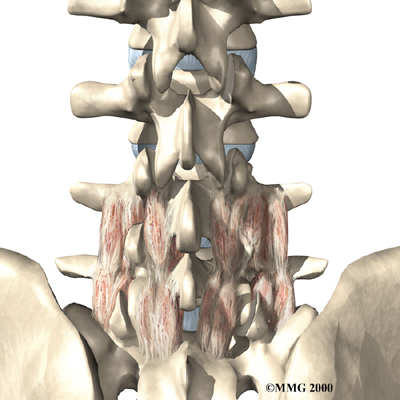

Posterior Lumbar Fusion

Lumbar disc herniation causes mechanical pain, the type of pain caused by wear and tear in the parts of the lumbar spine. Fusion surgery is mainly used to stop movement of the painful area by joining two or more vertebrae into one solid bone. This keeps the bones and joints from moving, easing mechanical pain.

In posterior lumbar fusion, the surgeon lays small grafts of bone over the problem area on the back of the spinal column. Most surgeons will also apply metal plates and screws to prevent the problem vertebrae from moving. This protects the graft so it can heal better and faster.

Related Document: FYZICAL Balcones Guide to Posterior Lumbar Fusion